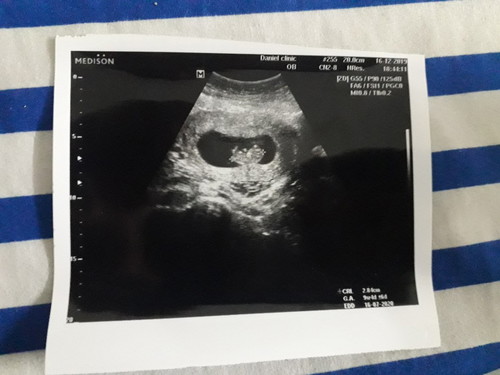

วันนี้คุณหมอนัดฟังผลเลือด และตรวจลูกน้อยในครรภ์ ทุกอย่างปกติ แม่รู้สึกปลื้มใจมากค่ะ ตอนนี้ 9w+ แล้ว คุณแม่ๆกี่วีคกันแล้วบ้างค่ะ